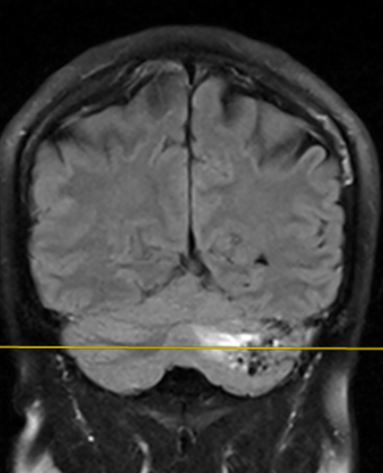

Figura 2: imagine în plan oblic coronal în ponderație FLAIR cu evidențierea nidusului şi a plajei cortico-subcorticale în hipersemnal din parenchimul cerebral al emisferului cerebelos stâng.